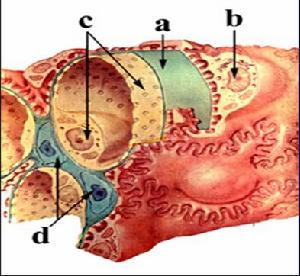

1.光鏡在疾病的早期階段,腎小球可能正常,也可能呈現局灶節段性硬化,系膜細胞及系膜基質增生;腎小管呈現囊性擴張。在疾病的晚期階段,腎小球毛細血管襻塌陷,呈現瀰漫性硬化;腎小管廣泛擴張、萎縮;間質炎症細胞浸潤及纖維化。在DMS的早期階段僅有足突細胞的肥大、足突的融合,系膜基質的增殖;晚期階段,大多數腎小球呈皺縮硬化的毛細血管襻沿著空泡變性的上皮細胞排列,小管萎縮、炎症細胞浸潤、間質纖維化。

2.免疫螢光早期正常;晚期在系膜區可有少量的IgM和C3沉積。可以是陰性,在系膜區或硬化的腎小球區域可能有IgM、C1q、C3沉積。

3.電鏡內皮細胞腫脹,上皮細胞足突融合,基膜皺縮等。基膜不規則增厚,正常的三層結構代之以一層雜亂無章、透明的、電子緻密物,在基膜可見到大量的細絲狀物質,足突融合,系膜基質膨脹。

(1)芬蘭型:腎臟病理檢查光鏡下特徵為近曲小管呈囊樣擴張,因此從前曾將此病命名為嬰兒微囊病。早期腎小球正常,而後系膜增生,晚期腎小球硬化伴間質纖維化。電鏡顯示腎小球髒層上皮細胞瀰漫足突融合。免疫螢光檢查陰性。

(2)非芬蘭型:腎髒病理表現為瀰漫性腎小球系膜硬化或局灶腎小球硬化。